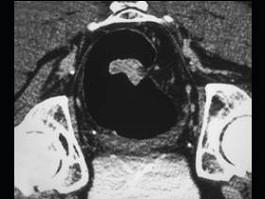

问题 男,56岁,下腹疼痛、大便潜血阳性,结合图像应考虑为 ( )

选项 A、直肠间质瘤 B、直肠淋巴瘤 C、直肠癌 D、直肠腺瘤 E、直肠息肉

答案 C